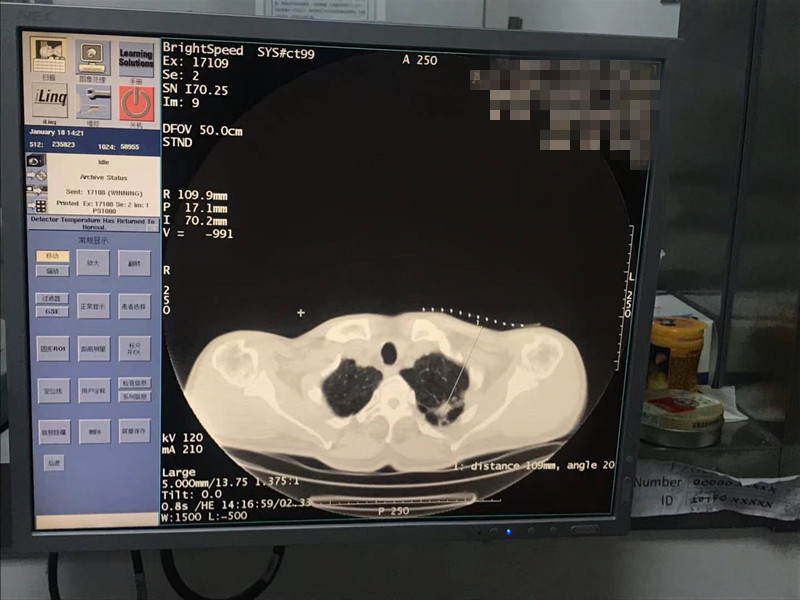

2021年1月份肺部氩氦刀手术

发布人:美国氩氦刀技术官方网站    发布时间:2021/9/22 15:39:30